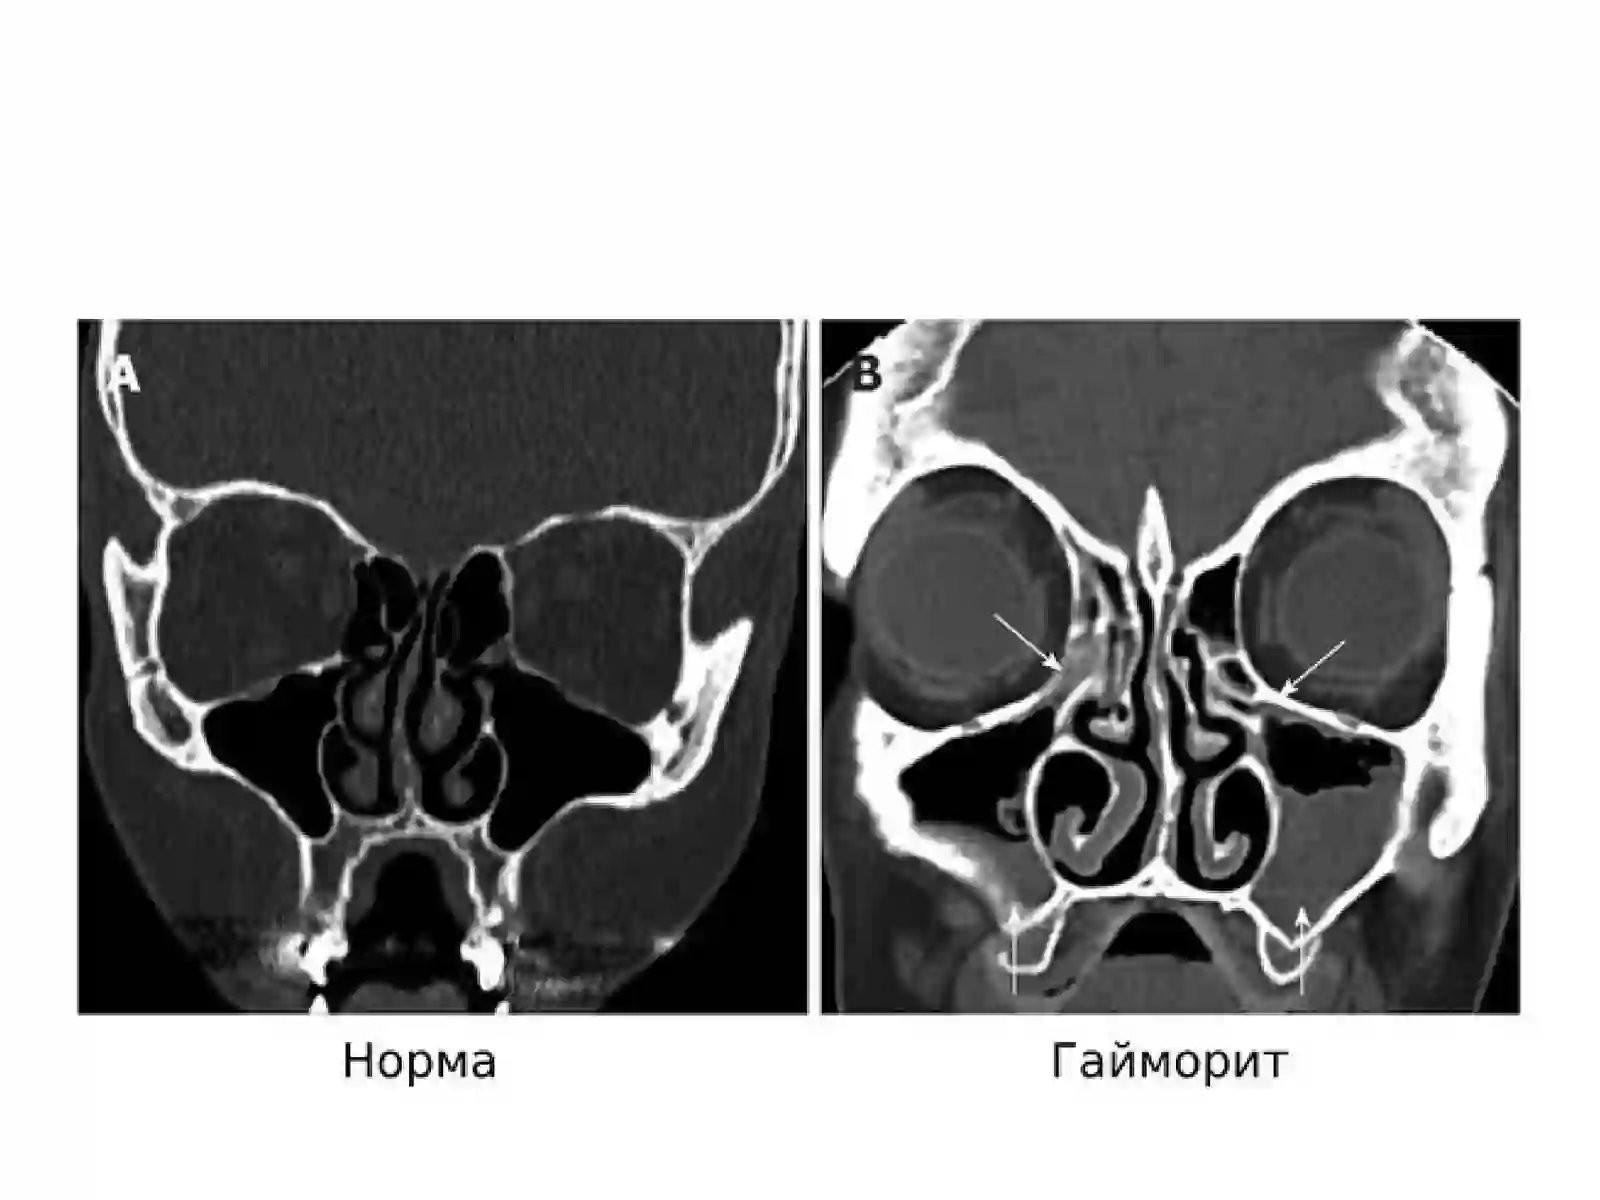

Saidaxmatov Alisherxon va uning jamoasi tomonidan burun va yondosh bo'shliqlari 3D rentgeni va konusno-luchevaya kompyuter tomografiyasi bilan kasalliklar tashxisi va davolash ishlarini olib boradilar